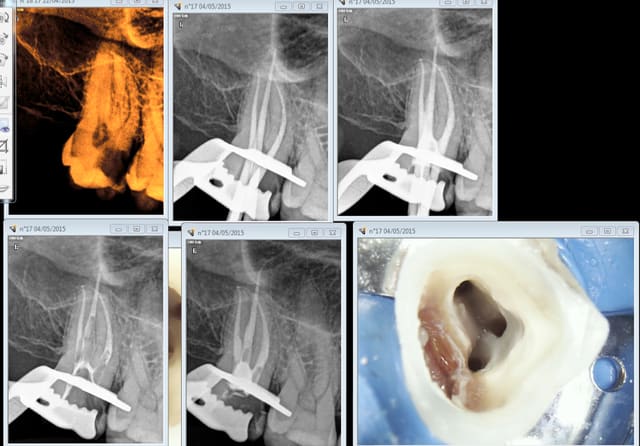

Voilà à quoi ressemble le mien juste après une endo. C'est du bordel organisé ! -))))

Ah oui le résultat de l'endo ce qui est le principal. Avec un jeu de limes K et un lentulo je n'aurais pas pu obtenir ce résultat, hein !